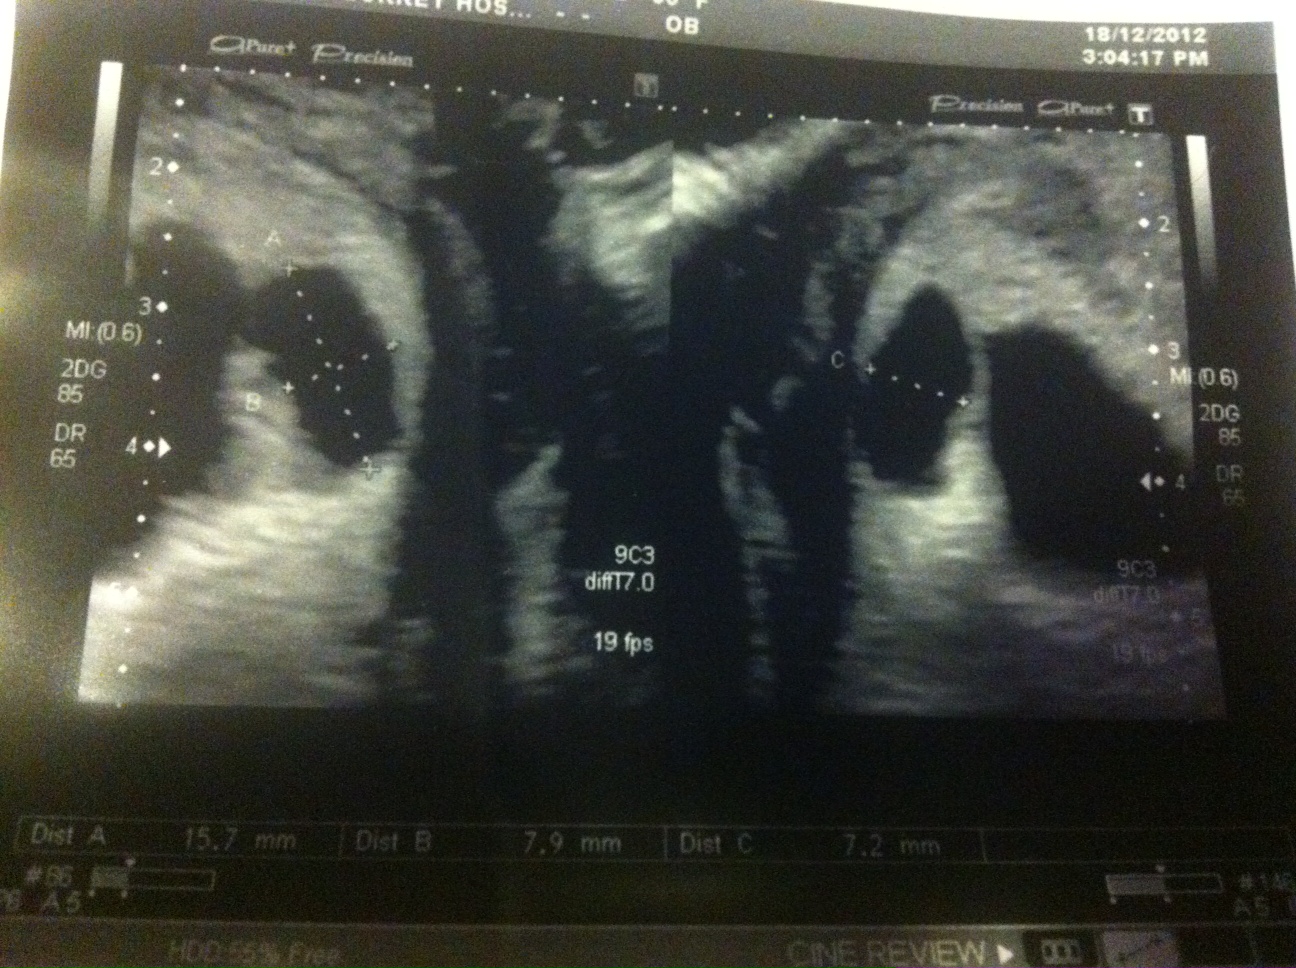

These are the pictures I got:

Attachment 7592

I then had a second (private) scan 6 days later and there were still 2 sacs yet this time it appeared there was a healthy baby in the big sac with yolk sac and heart beat and a CRL measurement of 13.8mm making it 7+5. The smaller sac still had an embryo and a tiny fetal pole but no heartbeat measured 3.6mm